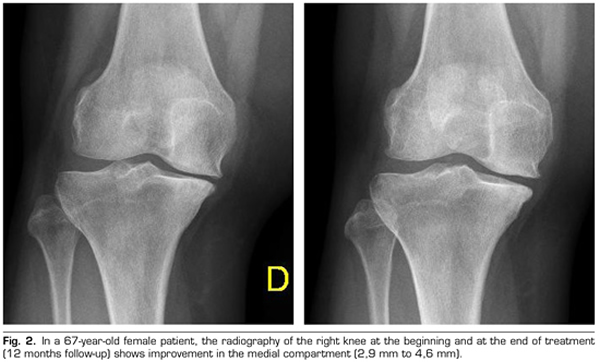

Regarding the radiological variables, when evaluating 53 out of the 115 patients who completed one year of follow-up after ozone treatment, it was observed that the internal compartment increased significantly by 4.12 ± 1.41 mm to 4.4 ± 1.35 mm (p = 0.0008) and the external compartment increased from 6 ± 1.37 to 6.16 ± 1.4 mm (p = 0.0753) (Table II). Two clinical cases are presented as a sample of the radiological change in the internal and external compartments (Figures 2 and 3).

After a year of follow-up with radiological controls on 53 out of the 115 patients in the study, ozone (O2-O3) has been able to increase the minimum joint space of the medial compartment (from 4.12 to 4.44 mm) and the lateral compartment (from 6.0 to 6.16 mm), reversing knee osteoarthritis in our case series. This finding suggests the disease modifying effect of ozone (O2-O3) on knee osteoarthritis, findings that is consistent with the recently reported by Fernández-Cuadros et al. (9).